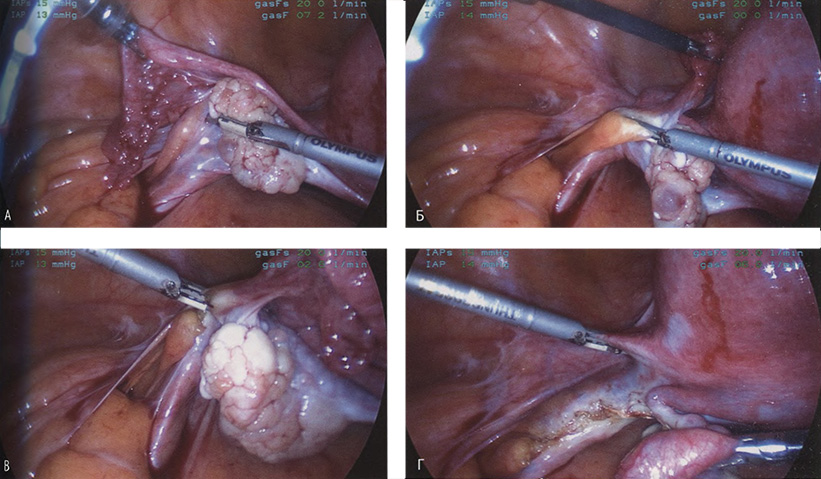

Если оставить в стороне эти достоинства и недостатки, то техника лапароскопической гистерэктомии фактически идентична технике лапаротомической гистерэктомии. В самом начале операции, если она выполняется лапароскопическим методом, необходимо осмотреть всё операционное поле, воспользовавшись для этого панорамным обзором (рис. 12-33—12-37). Операцию начинают с коагуляции и пересечения круглых связок, чем обеспечивается доступ к широкой связке (рис. 12-38—12-40). Брюшину, переходящую с купола мочевого пузыря на переднюю поверхность матки, вскрывают. Пузырь отсепаровывают от матки острым путём (рис. 12-41). После этого вскрывают задний листок широкой связки, а затем принимают решение, оставлять или удалять яичники. Если принято решение оставить яичники, то коагулируют и пересекают собственные связки яичников и маточные трубы (рис. 12-42). Если принято решение удалить яичники (то есть выполнить сальпингоофорэктомию), то с обеих сторон выполняют диссекцию мочеточников от воронко-тазовых связок, которые затем отсепаровывают, коагулируют и пересекают (рис. 12-43). Затем ткань широкой связки отделяют от маточных сосудов (отпрепаровывая их), изолировав, таким образом, мочеточники от маточных сосудов (рис. 12-44 А). Восходящие ветви маточных сосудов коагулируют справа и слева, а затем пересекают (рис. 12-44 Б, В).

Рис. 12-43. А. Представлен момент пересечения воронко-тазовой связки. Яичник оттянут для того, чтобы вызвать натяжение воронко-тазовой связки, с целью её лучшей визуализации. Б. Захват зажимом воронко-тазовой связки. В. Коагуляция и пересечение связки. Г. Воронко-тазовая связка пересечена.